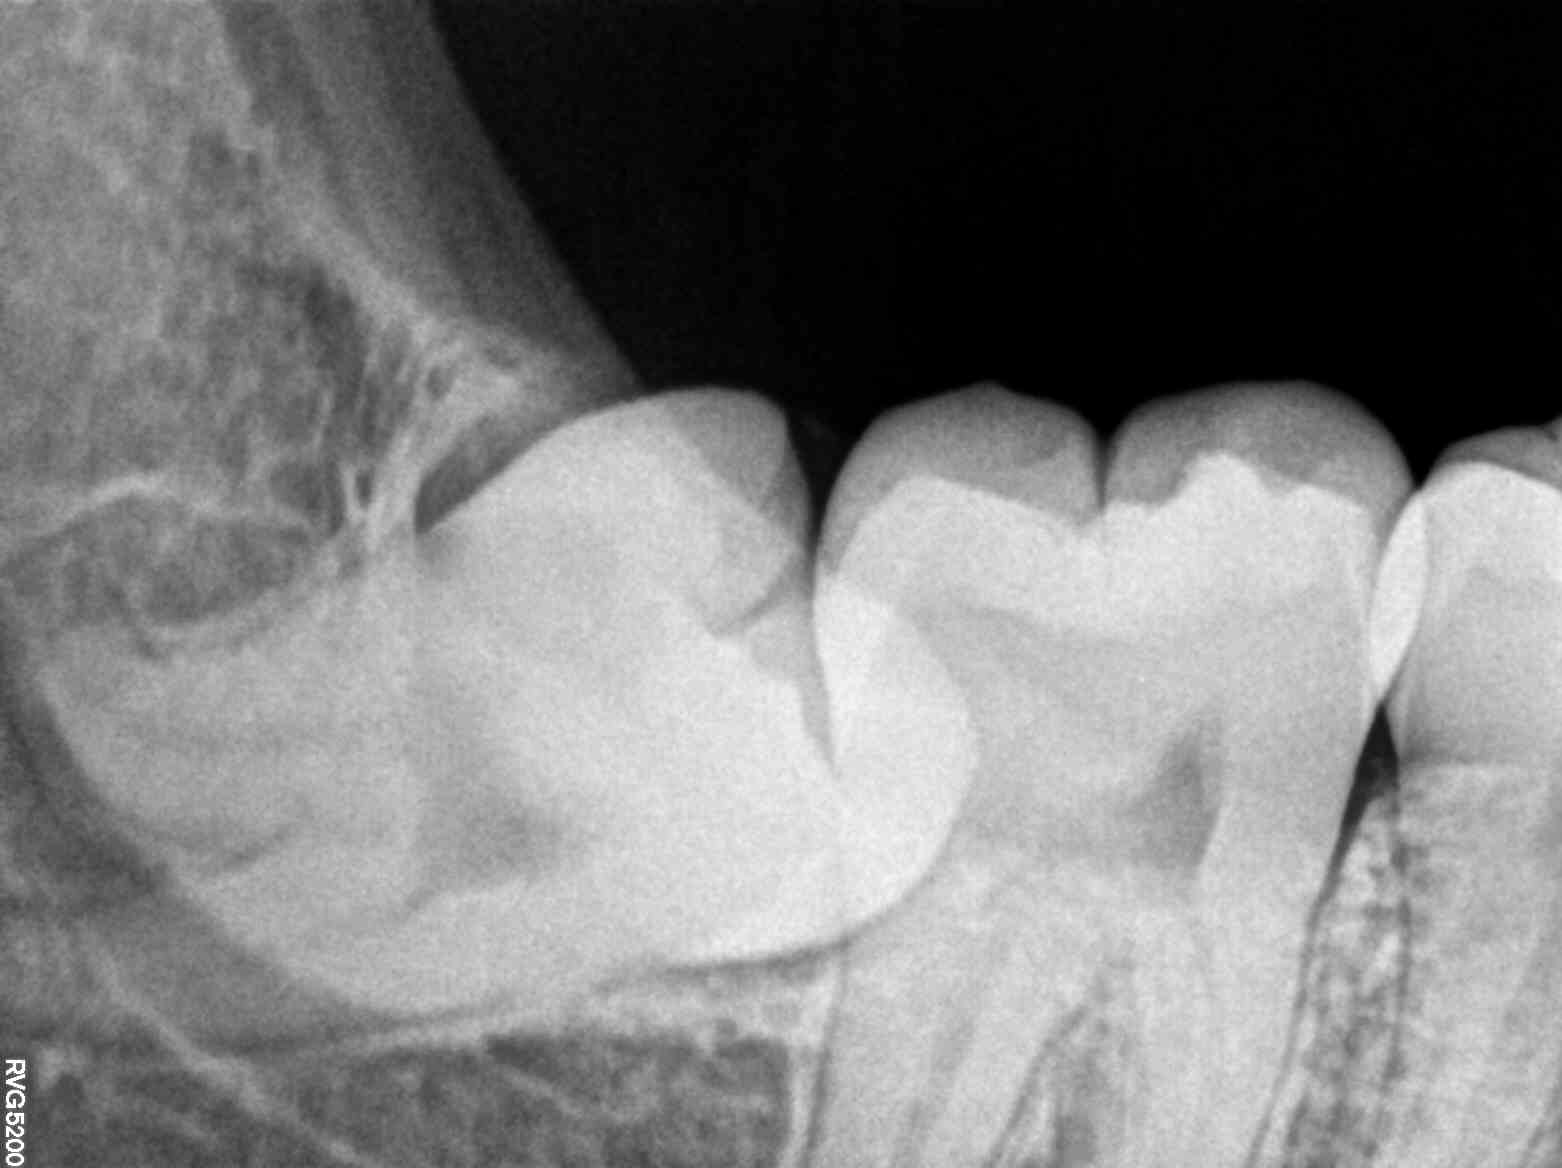

Imagine stepping into a clinic where a simple, painless X-ray scan unveils detailed images of your dental structure. This advanced technology detects cavities, gum diseases, and other anomalies with unparalleled accuracy, allowing for early intervention and less invasive treatments.

As she sat comfortably, the X-ray machine whirred gently, capturing high-resolution images of her teeth and jaw. Within moments, Dr. Rajesh was able to identify a small cavity and a minor alignment issue—problems that could have escalated without timely detection.